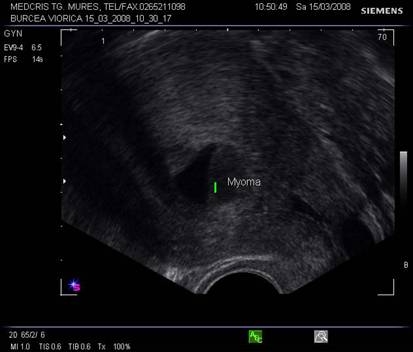

Fibromul uterin - cea mai frecvent intalnita tumora genitala, cu frecventa de 20 - 50% din femei [3].

Aproximativ 90% din fibroame (leiomioame) apar la nivelul corpului uterin. Se descriu, faza miomatozei difuze, fibroame intramurale, subseroase, submucoase, intraligamentare.Mioamele prezinta margini bine delimitate fata de miometru la ecografie, continand arii de mai mare sau mai mica ecogenitate in functie de modificarile degenerative.[1,6]

Fig. nr.385. Nodul submucos ce deformeaza cavitatea uterina, ecografie transvaginala